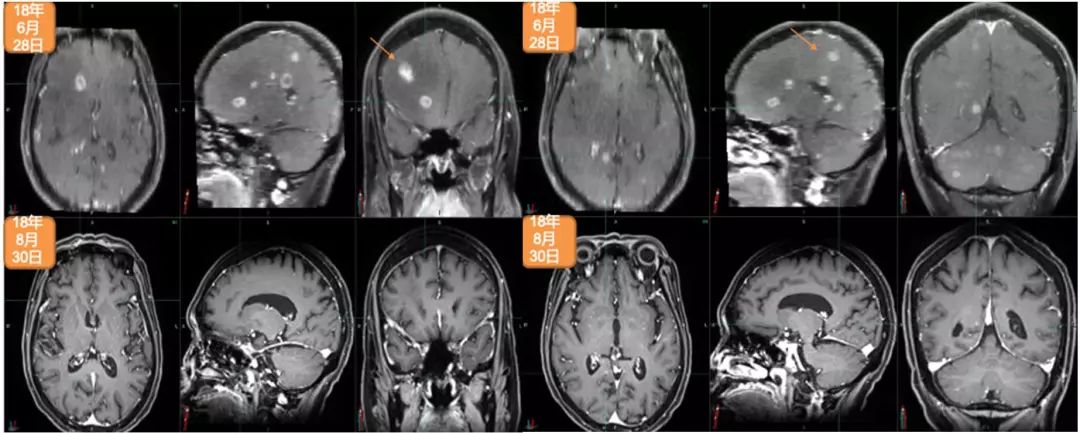

2018年5月,出现全身状况下降。2018年6月28日,进行脑部MRI检查:多发脑转移,右额叶最大病灶达2.5cm。2018年7月4日,进行PET/CT检查:多发纵隔淋巴结、胸腔和骨转移。2018年7月5日,进行右髂骨活检:转移性腺癌,原发于乳腺(BRST2+),ER-,PR-,HER2++,FISH+,Ki67:20%。

2018年7月12日至2018年7月25日期间,进行姑息性海马保护性全脑照射:30Gy,10次分割 。2018年6月15日开始姑息性TDM-1(Kadcyla®)200mg治疗。2018年12月7日,进行第8个周期治疗。2018年8月30日,进行脑部MRI检查:疾病缓解,右额叶最大病灶缩小至1.12cm。2018年8月31日,进行PET/CT检查:疾病缓解,包括胸腔积液缓解、肺原发灶、淋巴结和骨转移灶缩小并被吸收。治疗过程中仅有轻度不适,未出现显著的骨髓抑制或肝炎。Hb:11.1–12.2g/L;WBC:3.01–3.57×109/L;血小板:69-79(G2)。2018年12月28日开始下一个周期治疗。

2018年6月28日与2018年8月30日头颅MRI对比